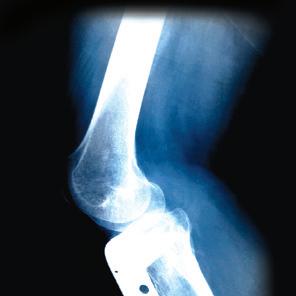

Any baby boomer will tell you that you’re never too old to try something new. But if your latest activity is a bit risky, you might want to know a first-class orthopedic specialist.

Plaza Medical Center is home to some of the leading orthopedic pioneers in Texas. Our renowned team of orthopedists is the first in Texas and the only one in Fort Worth to earn Joint Commission certification for hip and knee replacement. We’re also Fort Worth’s most experienced team: Last year, we performed more than 2,000 surgical procedures, from routine, minimally-invasive hip, knee and joint repairs to total reconstructions.

We want all of our patients to be physically able to take on exciting new challenges. It’s that simple. We do difficult. You do life. It happens every day at a place called Plaza.